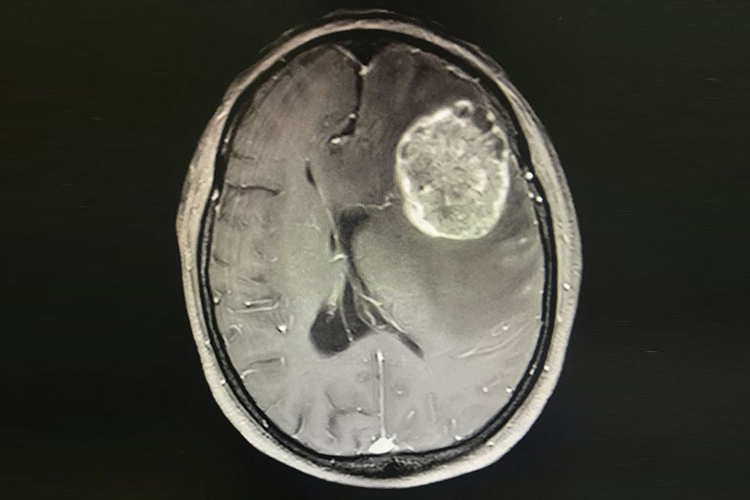

患者行脑部CT、核磁共振等影像学检查,可发现脑室系统的变性与移位,颅内密度减低区提示存在囊肿、软化灶,核磁共振可发现异常低信号、高信号,可显示整个脑癌肿物。由于脑癌肿物对周围脑组织产生压迫,可引起运动、语言、视觉等功能异常。